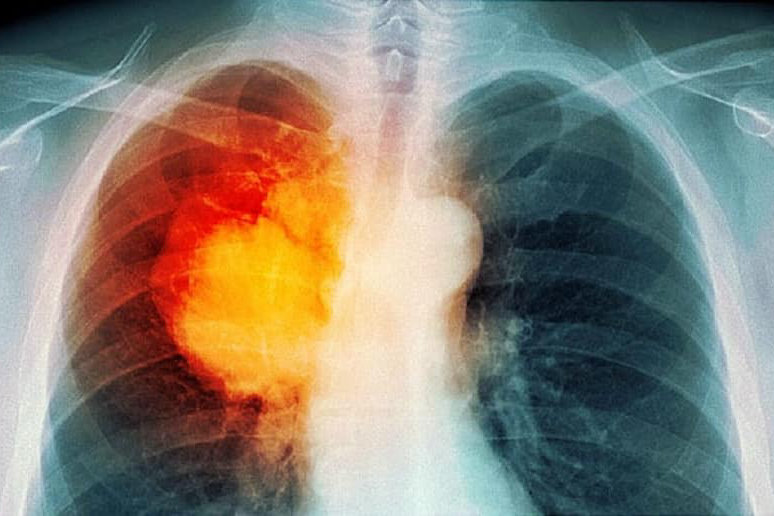

Hiện nay, theo các kết quả nghiên cứu, bệnh ung thư phổi được chia thành 2 loại: ung thư phổi tế bào nhỏ và ung thư phổi không tế bào nhỏ.